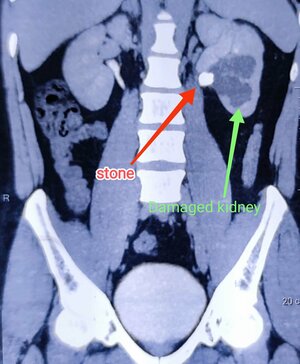

Not all Stones are stepping stones

? “Not All Stones Are Stepping Stones” ? Some Stones Can Harm Your Kidneys Diagnosed with a Kidney or Ureteric Stone on Ultrasound o...

Kidney Stone

किडनी स्टोनचा त्रास दुर...